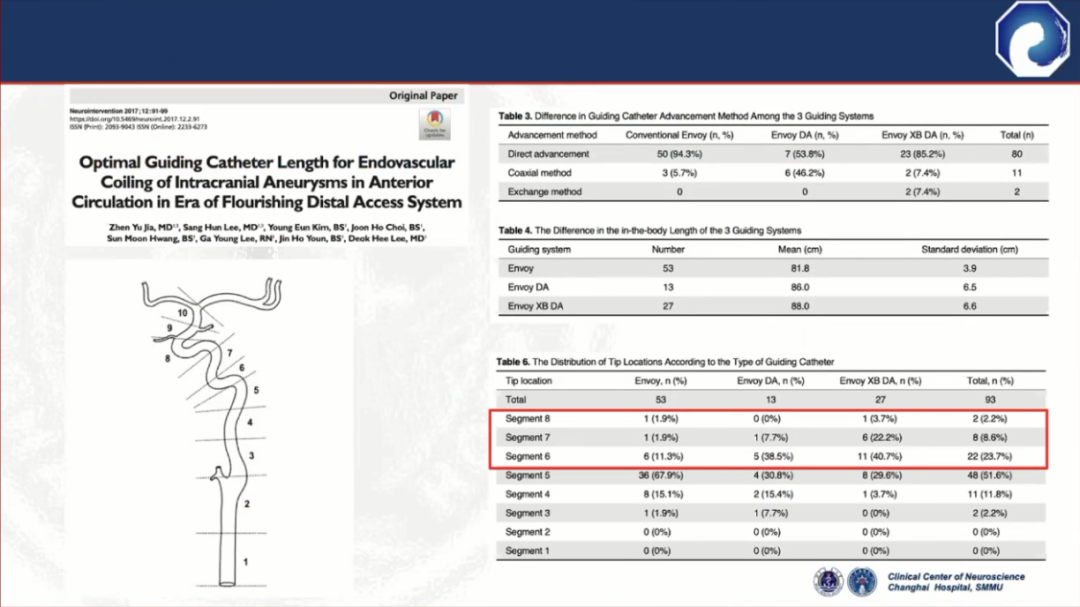

头端到位低,不适合远端病变

此外,中间导管的支撑力比较差,近端需加长鞘或8F Guiding做支撑,需三轴系统

三轴系统的缺点:

远端通路导引导管既具备传统导管的近端支撑能力,又具备中间导管的远端通过能力

与三轴系统相比,双轴系统显著缩短了手术时间,降低潜在并发症发生率